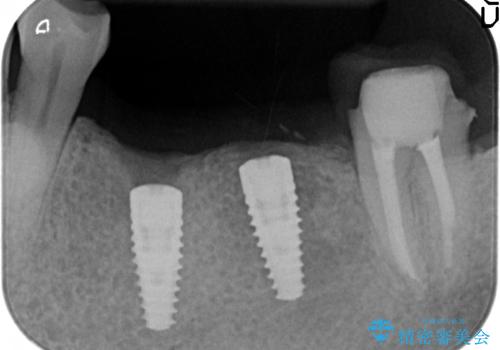

欠損部位である左下5、6番目にインプラントを埋入し、オールセラミッククラウンによる補綴を行いました。

- オールセラミッククラウン…¥100,000×3、仮歯…¥10,000×3、インプラント(ストローマン)…¥200,000×2、カスタムアバット…¥100,000×2、ファイバーコア…¥20,000、根管治療費別途費用は治療当時の料金となります

当院では主にストローマンという種類のインプラントを治療に用いています。

ストローマンは世界的にもNo1のシェアを誇り、骨との適合にも優れたインプラントです。